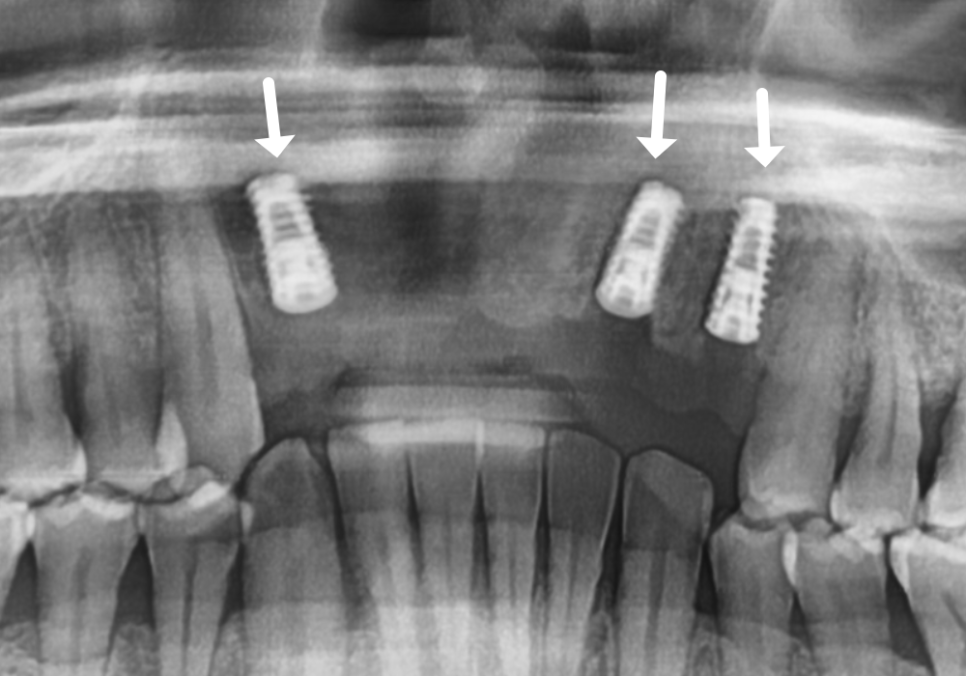

이번 환자분의 경우에도 CT를 분석해 보니

다행히 뼈의 폭이 5mm~7mm 정도로

충분히 두꺼웠습니다.

뼈의 폭이 충분하다면

굳이 뼈이식을 할 필요가 없습니다.^^

만약 뼈의 폭이 너무 얇다면

임플란트 식립이 힘들기 때문에

뼈의 폭을 늘리는 뼈이식이 필수적이지만,

이 환자분은 뼈가 건강하셨기에

추가적인 뼈이식 없이

총 3대의 임플란트를

정확한 위치에 식립해 드렸습니다.